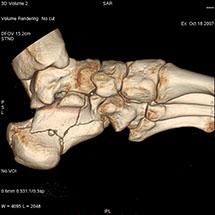

Le scanner comporte un lit d'examen, sur lequel le patient est allongé, qui va se déplacer lentement pendant l’examen et un anneau qui va tourner autour du patient en émettant des rayons X (il contient le tube à rayons X et les récepteurs). Les rayons X vont traverser la région à étudier et permettre d’obtenir des images en coupe de la zone à étudier. Des traitements de numérisation informatique permettront d'obtenir  des images 2D ou 3D dans différents plans et volumes.

• Les examens et mesures orthopédiques (malformations, fractures et évolution, étude de la structure osseuse).